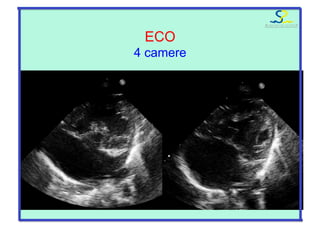

ECO

ipoVS

“4” camere: ipo VD/VS